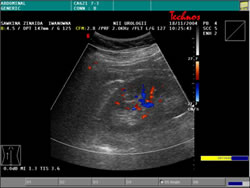

УЗИ: |

|